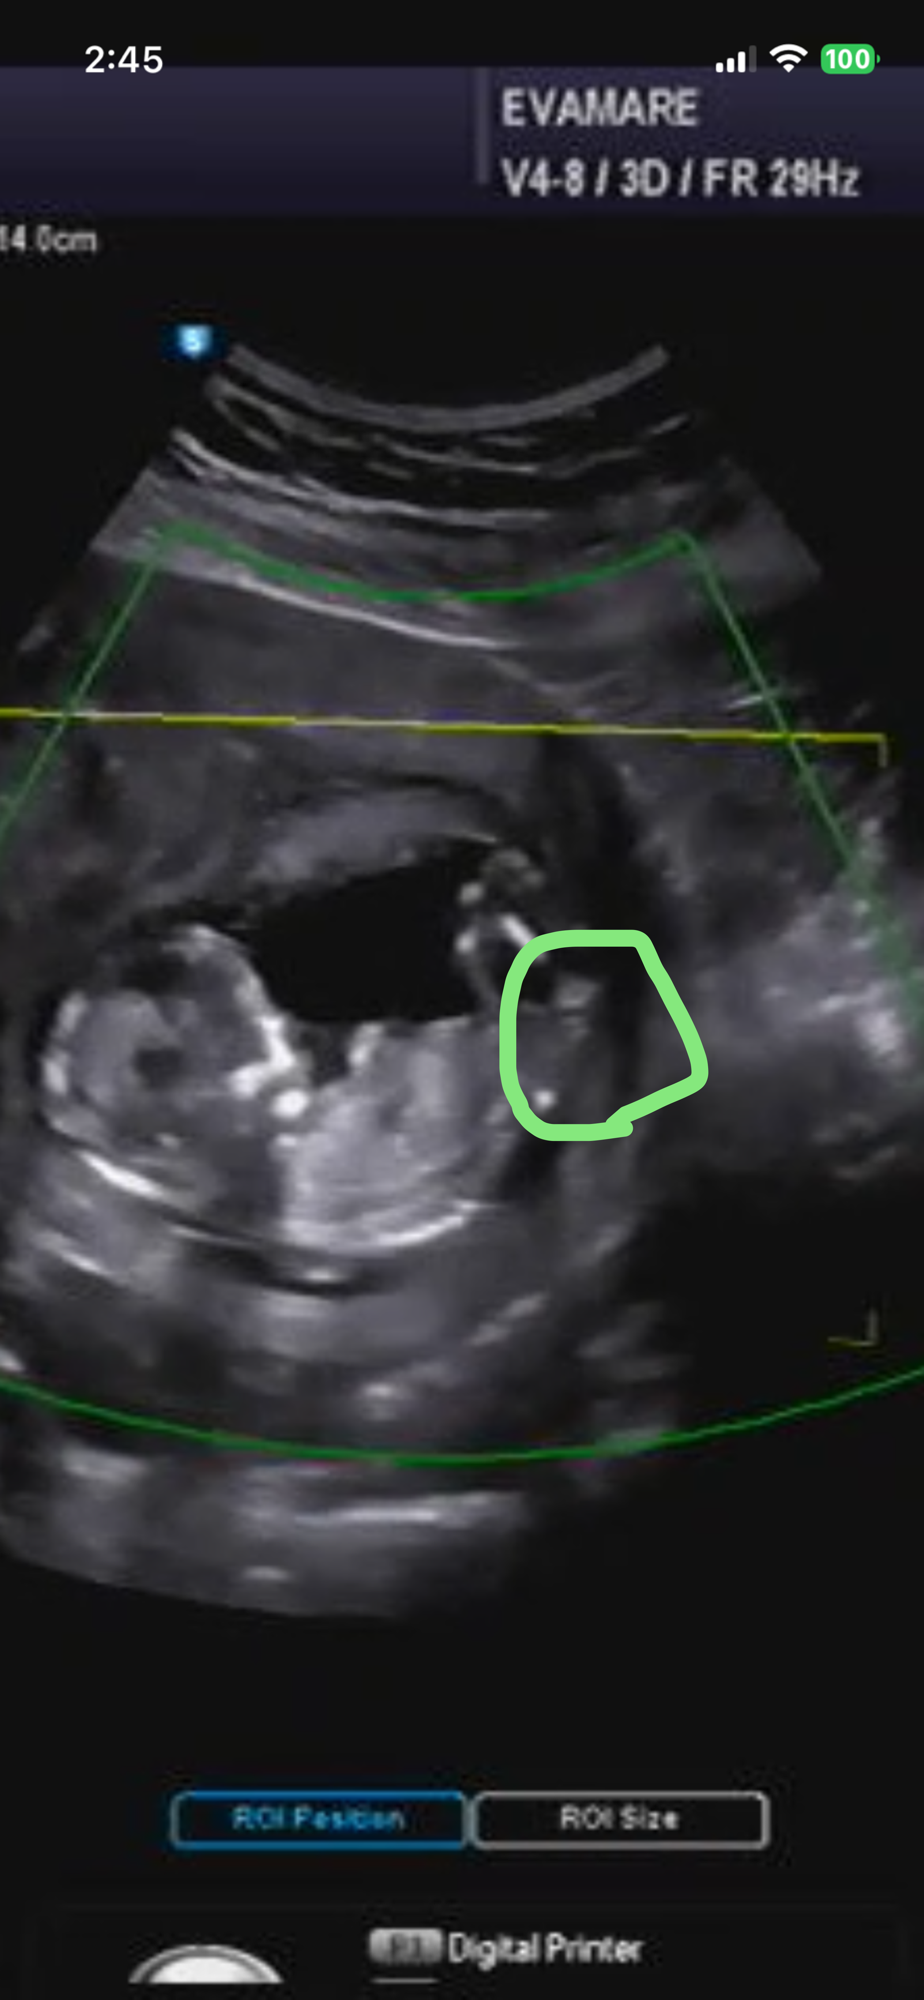

12주 초음파 성별

동그라미 표시 뭘로보이나요?